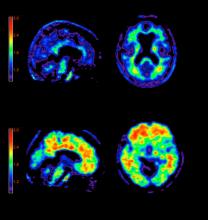

The last decade has seen a significant advancement in imaging technology due to developments in the hardware and software space. It was clear to the radiologists, clinicians and imaging scientists very early on that no single imaging modality, be it magnetic resonance imaging (MRI), computed tomography (CT) or positron emission tomography (PET) could meet all the needs of a clinician treating a patient.

The introduction of hybrid technology — positron emission tomography/computed tomography (PET/CT) and single-photon emission computed tomography (SPECT)/CT -— has revolutionized the imaging world. This technology allows the combination of the exquisite anatomic details provided, for example, by CT, with the important and much needed functional, physiologic or metabolic information provided by molecular imaging.